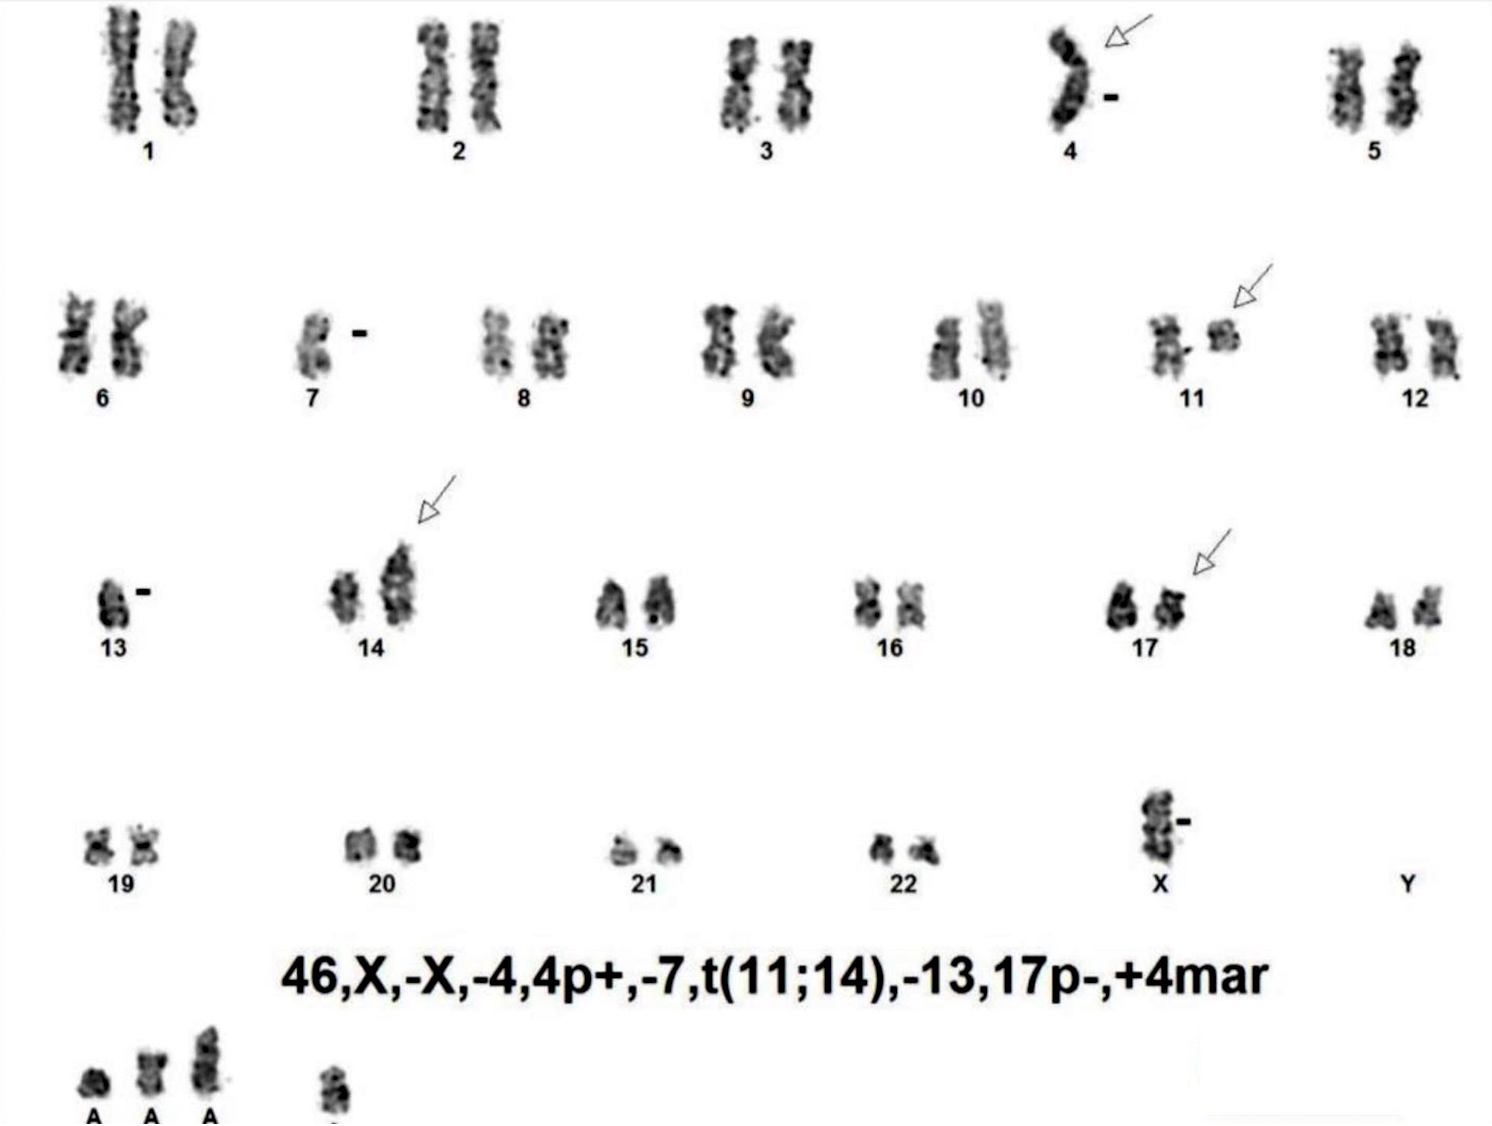

Molecular / cytogenetics description

- Karyotypes are often complex (≥ 3 abnormalities)

- Tetraploid clones are more frequently found in pleomorphic (80%) and blastoid (36%) variants

- Some abnormalities may be specifically involved in pathogenesis

- Chromosome 17p deletions (TP53)

- Chromosome 9p deletions (CDKN2A)

- Chromosome 8q24 translocations or amplification (MYC)

- Chromosome 3q27translocations (BCL6)

- t(11;14)(q13;q32)

- Aggressive variants of mantle cell lymphoma

- TP53 or p16 mutations are common

- t(8;14)(q24;q32)(IGH/MYC) in a small subset of cases

- Mutations in many genes

- ATM (~ 40%), TP53 (~ 25%), CDKN2A (TP16) (10 - 20%)

- Other mutations correlated with blastoid or pleomorphic variant

- KMT2D/MLL2 (~ 10%), WHSC1 (~ 10%), BIRC3 (~ 5%)

- NOTCH1 (~ 5%), NOTCH2 (~ 5%), MEF2B (~ 3%), MYD88 (~ 1%)

- CARD11 (10%)

Molecular / cytogenetics images